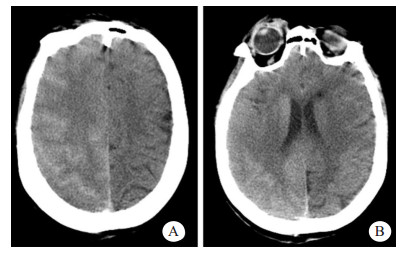

患者女性,71岁,2011年3月行食管癌切除术,6年来反复出现咯血症状,每次均在止血及抗感染治疗后好转。2018年1月20日患者再次出现咯血,入苏州大学附属第二医院介入科治疗。CT检查提示支气管扩张伴感染,遂于2018年1月25日在本院行支气管动脉栓塞术,分别对右支气管动脉远端、支气管动脉主干及左侧肋间动脉进行栓塞,术中使用的造影剂为碘海醇150 mL(浓度为30 g/100 mL)。术后仍出现反复痰中带血,因症状逐渐加重,患者于2018年8月13日再次来本院就诊。患者既往无高血压、糖尿病、心脏病等慢性病病史。入院后,给予患者头孢匹胺抗感染及止血、抑酸等对症支持治疗,咯血症状明显缓解。为进一步明确患者支气管动脉情况并予以处理,于8月17日穿刺右股动脉对患者施行支气管动脉造影+栓塞术,造影显示左侧两支支气管动脉与肋间动脉共干,左侧一支气管动脉血管明显增粗,紊乱,可见小片状可疑出血染色,遂对左侧两支与肋间动脉共干的支气管动脉分别予以栓塞,术中使用的造影剂为碘海醇100 mL(浓度为30 g/100 mL)。术中患者未有不适,术后患者安返病房。术后2 h, 患者无明显诱因下突然出现谵妄,查体:T 36.6℃,P 110次/min,BP 190/80 mmHg (1 mmHg=0.133 kPa),双侧瞳孔对光反射存在,左上肢肌力1级,右上肢肌力5级。急诊颅脑CT显示,右侧脑沟裂、纵裂池密度增高,局部脑实质肿胀、密度增高(图 1)。术后4 h颅脑MRI显示,右侧额叶部分皮质增厚,皮质T1WI信号稍减低,T2WI、T2WI-FLAIR、DWI信号增高,ADC信号稍高;右侧放射冠区见斑片状T1WI稍低信号,T2WI、T2WI-FLAIR、DWI高信号,ADC稍高信号影(图 2A~E);颅脑与颈部TOF-MRA显示各动脉未见明显扩张或狭窄征象。结合患者临床及影像学表现,在排除心脑血管病变后,经多学科会诊,考虑造影剂脑病。给予患者糖皮质激素抗炎、甘露醇降颅压、改善微循环及纠正电解质紊乱等对症处理,患者于术后第3天意识恢复,左侧肢体肌力明显好转。术后第6天,患者精神状态与左侧肢体肌力完全恢复,复查颅脑CT显示脑沟裂池内及局部脑实质高密度影消失,MRI各序列(图 2F~J)未见明显异常,予以出院,随访至今,患者未有不适。

| 患者介入栓塞术后2 h,示右脑沟裂、纵裂池密度增高(A),局部脑实质肿胀、密度增高(B) 图 1 患者颅脑CT检查结果 |

临床表现轻微的造影剂脑病,影像学检查可以无异常发现。对于症状较为严重的患者,颅脑CT平扫及MRI检查常可见特征性表现。造影剂脑病的CT表现可以为脑水肿,皮质及皮质下异常高密度影,蛛网膜下腔密度增高以及局灶性高密度改变等[2, 6]。但是,有些造影剂脑病患者虽然症状严重,CT平扫也可无异常发现[4]。CT上脑实质的异常高密度影在MRI上可以表现为T2WI、DWI及FLAIR高信号灶,而ADC可无明显异常[3, 6]。这些异常的影像学表现均会在临床对症治疗后短期内消失。本例患者的CT及MRI表现与文献报道相符。

造影剂脑病需与部分脑血管疾病相鉴别,主要是蛛网膜下腔出血和急性缺血性梗死。蛛网膜下腔出血与造影剂脑病在CT上都可以表现为脑沟裂池内高密度影,但出血的CT值一般为40~60 HU,而进入脑沟裂池的造影剂CT值约为80~160 HU[3]。造影剂脑病的异常高密度影会在24~48 h内变淡甚至消失,但出血的高密度影常可持续数天至数周。不同时期的蛛网膜下腔出血在T2WI-FLAIR上均可表现为脑沟内高信号[7],而本例CT图像中脑沟裂池内的高密度影在T2WI-FLAIR上表现为与正常脑脊液类似的低信号。造影剂脑病患者可以出现类似急性缺血性梗死导致的头痛、偏瘫等神经系统症状,但急性缺血性梗死在ADC上表现为低信号,颅脑TOF-MRA常可见到脑血管的局限性狭窄或闭塞,本例患者ADC信号未见降低且颅脑TOF-MRA未见明显异常。